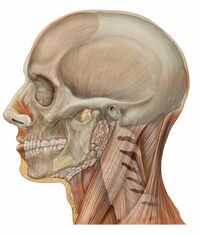

In the human, the skull comprises two prominent parts: the neurocranium and the facial skeleton,[3] which evolved from the first pharyngeal arch. The skull forms the frontmost portion of the axial skeleton and is a product of cephalization and vesicular enlargement of the brain, with several special senses structures such as the eyes, ears, nose, tongue and, in fish, specialized tactile organs such as barbels near the mouth.[4]

The skull is composed of three types of bone: cranial bones, facial bones and ossicles, which is made up of a number of fused flat and irregular bones. The cranial bones are joined at firm fibrous junctions called sutures and contains many foramina, fossae, processes, and sinuses. In zoology, the openings in the skull are called fenestrae, the most prominent of which is the foramen magnum, where the brainstem goes through to join the spinal cord.

In human anatomy, the neurocranium (or braincase), is further divided into the calvaria and the endocranium, together forming a cranial cavity that houses the brain. The interior periosteum forms part of the dura mater, the facial skeleton and splanchnocranium with the mandible being its largest bone. The mandible articulates with the temporal bones of the neurocranium at the paired temporomandibular joints. The skull itself articulates with the spinal column at the atlanto-occipital joint. The human skull fully develops two years after birth.

Functions of the skull include physical protection for the brain, providing attachments for neck muscles, facial muscles and muscles of mastication, providing fixed eye sockets and outer ears (ear canals and auricles) to enable stereoscopic vision and sound localisation, forming nasal and oral cavities that allow better olfaction, taste and digestion, and contributing to phonation by acoustic resonance within the cavities and sinuses. In some animals such as ungulates and elephants, the skull also has a function in anti-predator defense and sexual selection by providing the foundation for horns, antlers and tusks.

The human skull is the bone structure that forms the head in the human skeleton. It supports the structures of the face and forms a cavity for the brain. Like the skulls of other vertebrates, it protects the brain from injury.[6]

The skull consists of three parts, of different embryological origin—the neurocranium, the sutures, and the facial skeleton. The neurocranium (or braincase) forms the protective cranial cavity that surrounds and houses the brain and brainstem.[7] The upper areas of the cranial bones form the calvaria (skullcap). The facial skeleton (membranous viscerocranium) is formed by the bones supporting the face, and includes the mandible.

The human skull is generally considered to consist of 22 bones—eight cranial bones and fourteen facial skeleton bones. In the neurocranium these are the occipital bone, two temporal bones, two parietal bones, the sphenoid, ethmoid and frontal bones.

The bones of the facial skeleton (14) are the vomer, two inferior nasal conchae, two nasal bones, two maxilla, the mandible, two palatine bones, two zygomatic bones, and two lacrimal bones. Some sources count a paired bone as one, or the maxilla as having two bones (as its parts); some sources include the hyoid bone or the three ossicles of the middle ear, the malleus, incus, and stapes, but the overall general consensus of the number of bones in the human skull is the stated twenty-two.

Some of these bones—the occipital, parietal, frontal, in the neurocranium, and the nasal, lacrimal, and vomer, in the facial skeleton are flat bones.